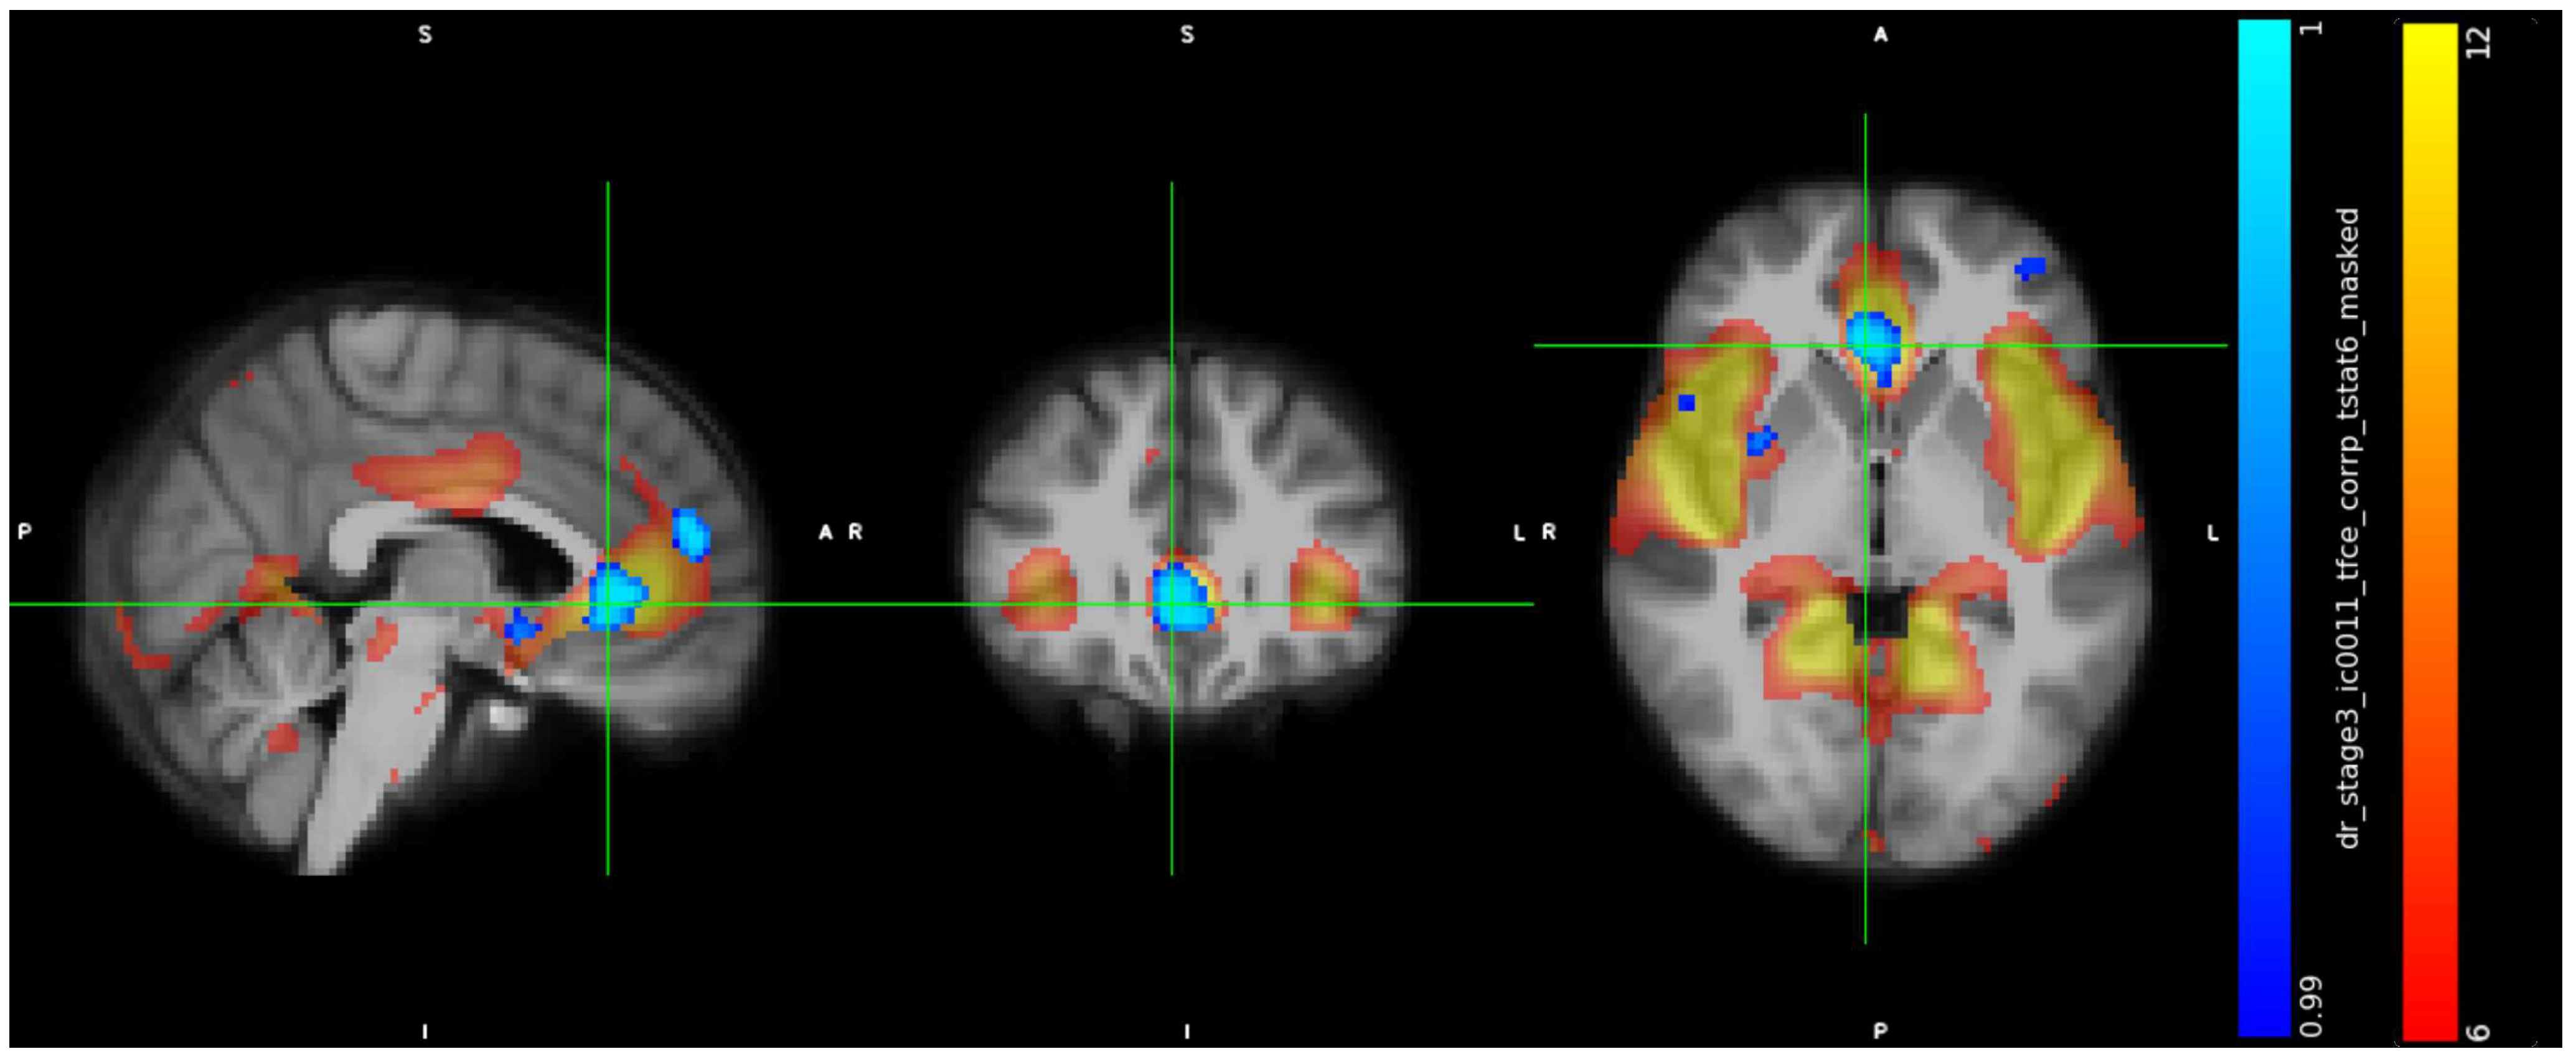

3.2. IC Analysis and Dual Regression